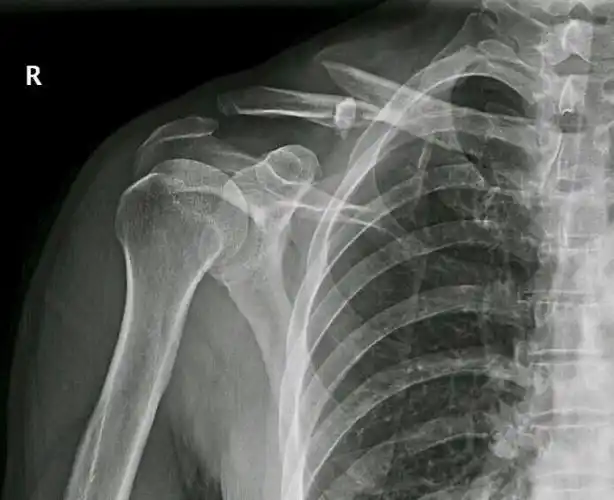

右侧锁骨骨折x线片